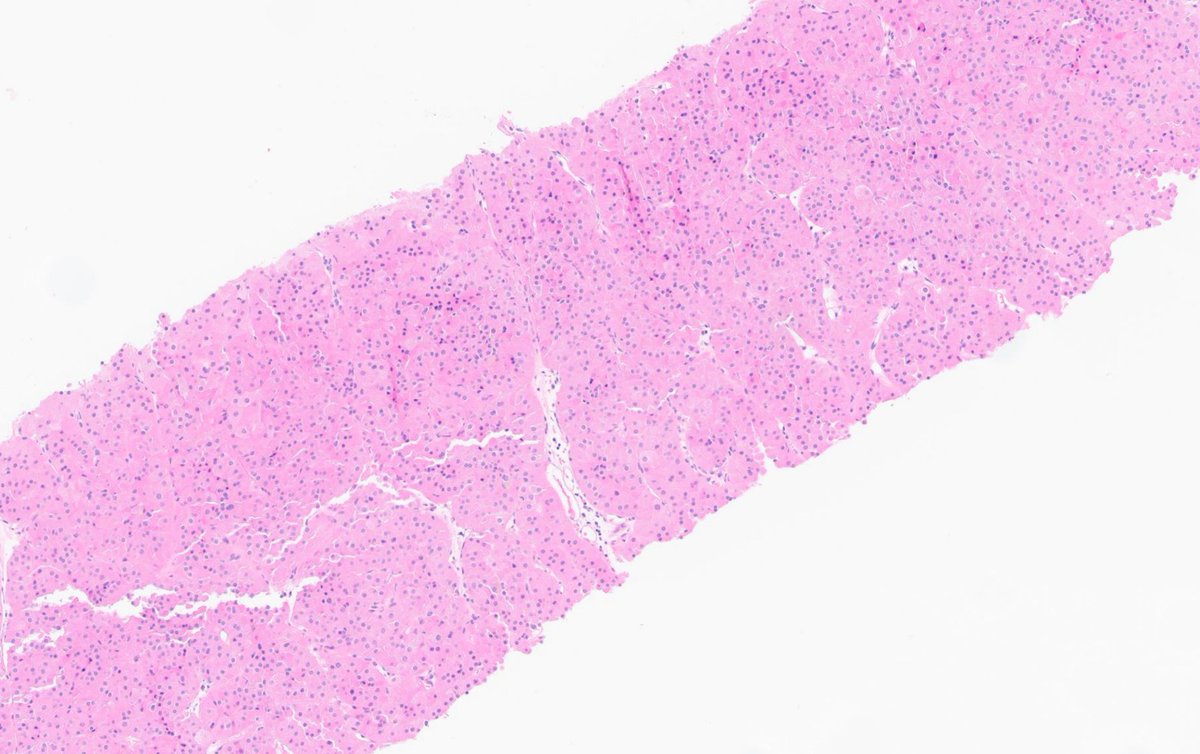

Prostate cancer w/foamy gland features - note the pyknotic nuclei in foamy glands = deceptively benign-appearing Fortunately, as in this example, often admixed with usual acinar #prostatecancer with more amphophilic cytoplasm, prominent nucleoli, etc. #gupath